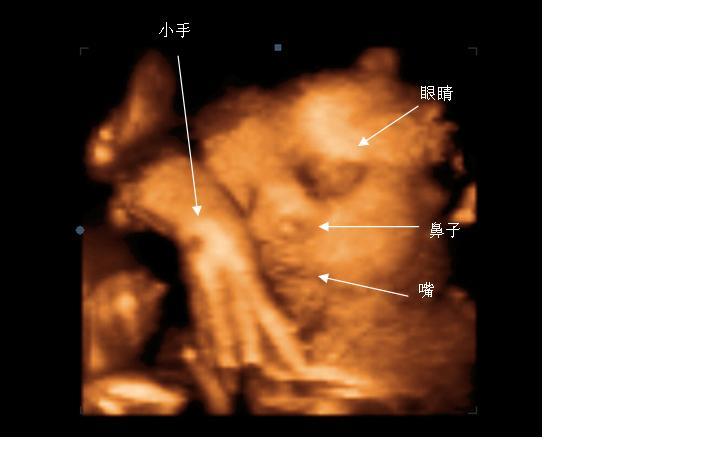

四维彩超 效果

四维彩超是动态的,三维彩超是静态的,所以四维看起来会更清楚明晰,三维彩超只能是某个时间点上的照片,四维彩超的就可以做成DV那样连续的,可以刻录光盘。

三维彩超和四维彩超的区别就是在于一个"时间维",也就是说,三维彩超说图片,四维彩超说录像,可以让孕妈妈看到胎儿一连串的动作。